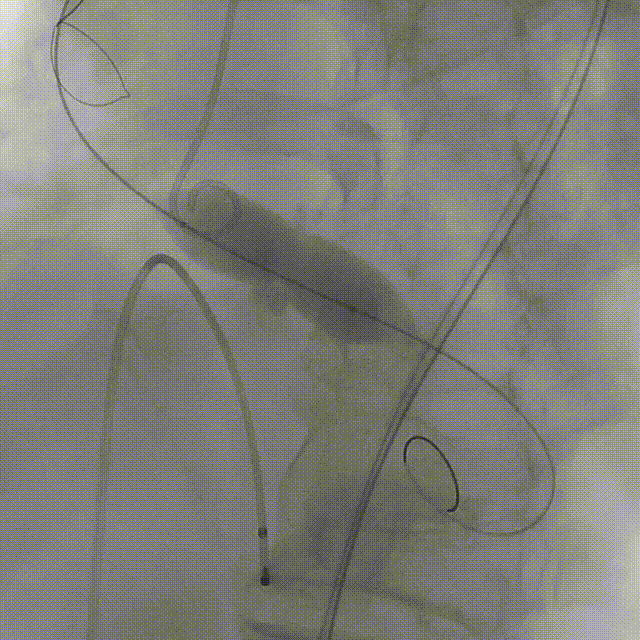

患者病史 主诉:发作性胸闷憋喘半年,加重伴呼吸困难2周。 现病史:患者半年前无明显诱因出现胸闷、憋喘,伴有下肢水肿,2周前上述症状明显加重,夜间不能平卧,痰中带血丝,为进一步诊治再次来我院,门诊以"心力衰竭"收入院。 既往史:肾功能不全、心房颤动 心脏超声提示:LVEF:0.54 1.主动脉瓣病变;2.主动脉瓣狭窄(重度)并反流(中度);3左室壁节段性运动不良;4.升主动脉扩张、双房扩大、左室肥厚;5.二尖瓣硬化并反流(中度);6.三尖瓣反流(轻-中度);7.肺动脉瓣反流;8.肺动脉高压(轻度)PGmean=105mmHg,Vmax=635cm/s,瓣口面积0.27cm²。 术前CT评估 Type0型二叶瓣,重度钙化,钙化集中在瓣叶游离缘,右冠窦为著;左冠高度11.8mm,由于左冠窦部空间较小,左冠风险较高, 升主动脉扩张,最宽处50.5mm;主动脉瓣环水平夹角61.5°,横位心。主动脉弓角77.6°,锐角弓,外周入路在腹主及髂总处有大量散状钙化,胸主处有81.6°的迂曲。 手术策略 推荐右侧股动脉为主入路,左侧股动脉为辅入路,送snare辅助过弯,使用18F大鞘,推荐预装ProStyle A® AV23瓣膜,20mm球囊预扩,初始定位对齐真实瓣环瓣上5mm超高位初始定位释放,释放过程中使瓣膜自然下滑,到工作位观察瓣膜形态,最终理想位置0-瓣下3mm。 手术过程 Step1:右侧股动脉为主入路、左侧股动脉为辅入路,成功穿刺并送入 18F 大鞘; Step2:主动脉根部造影,瓣口限制重 Step3:Type 0 型二叶瓣畸形合并重度钙化,患者瓣口狭窄严重,同时横位心,不仅导丝跨瓣困难,导管更难进入;术者凭借精湛操作,将导丝顺利跨瓣,反复微调导管角度,最终导管顺利过瓣。 导丝精准跨瓣 Step4:20mm球囊跨瓣困难,snare辅助下球囊成功跨瓣,预扩有腰无漏,冠脉充盈良好。 Step5: snare辅助下成功跨瓣,可以看到系统过弓形态瓣膜仓柔软,过弓顺滑 输送系统过弓 Step6:初始定位瓣上5mm开始释放,释放部分后观察瓣架下缘内收明显,后回收系统重新定位 初始定位 底部内收 Step7:瓣膜完全释放前,血压一度降低,术者迅速调整器械,实现瓣膜迅速锚定,快速释放 完全释放 Step8:20mm球囊后扩 最终造影,位置(瓣下3mm)形态良好 手术难点 患者不仅有主动脉瓣重度狭窄,还叠加肾功能不全、心房颤动等基础疾病,术中血流动力学波动极易引发心功能衰竭。ProStyle A® 预装干瓣“开包即用” 的特性压缩了术者操作时间,80%可回收设计给了术者容错空间,而这些看似难以逾越的难关,最终被团队精湛的医术一一化解,术中对于导丝、导管、球囊等器械每一步的精准操控,再到突发状况的从容处置,无不彰显着团队深厚的专业积淀与顶尖的操作技艺。 结语 此次手术的圆满成功,不仅彰显了陈玉国、李传保教授团队在复杂结构性心脏病介入治疗领域深厚的专业造诣与攻坚克难的决心,也充分验证了ProStyle A®系统在应对复杂高难度病例时的卓越适用性与有效性。 作为扎根齐鲁、享誉全国的医疗高地,山东大学齐鲁医院始终赓续着这片热土的仁厚文脉,将“医道从德,术业求精”的院训精神镌刻在每一次诊疗实践之中。特别是在结构性心脏病诊疗领域,医院团队始终怀揣医者担当,勇攀医学高峰,不断以更前沿的技术突破,为危重患者点亮重获新生的希望。 专家简介 陈玉国 山东大学齐鲁医院(点击查看专家详细简历) 李传保 山东大学齐鲁医院(点击查看专家详细简历) · END ·

根部造影